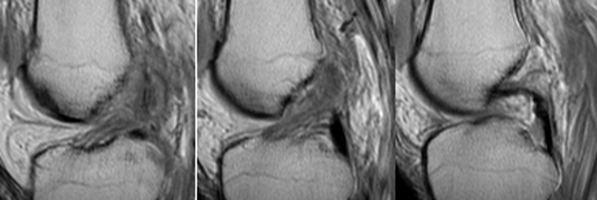

Segond Fracture

This eponym refers to a an avulsion fracture of the lateral tibial plateau at the site of attachment of the lateral capsular ligament. It is frequently associated with tears of the anterior cruciate ligament (70 % predictive) or menisci.

- Click on the image for a larger versionBSagittal MRI. This sequence of images of the knee shows disruption of the ACL.